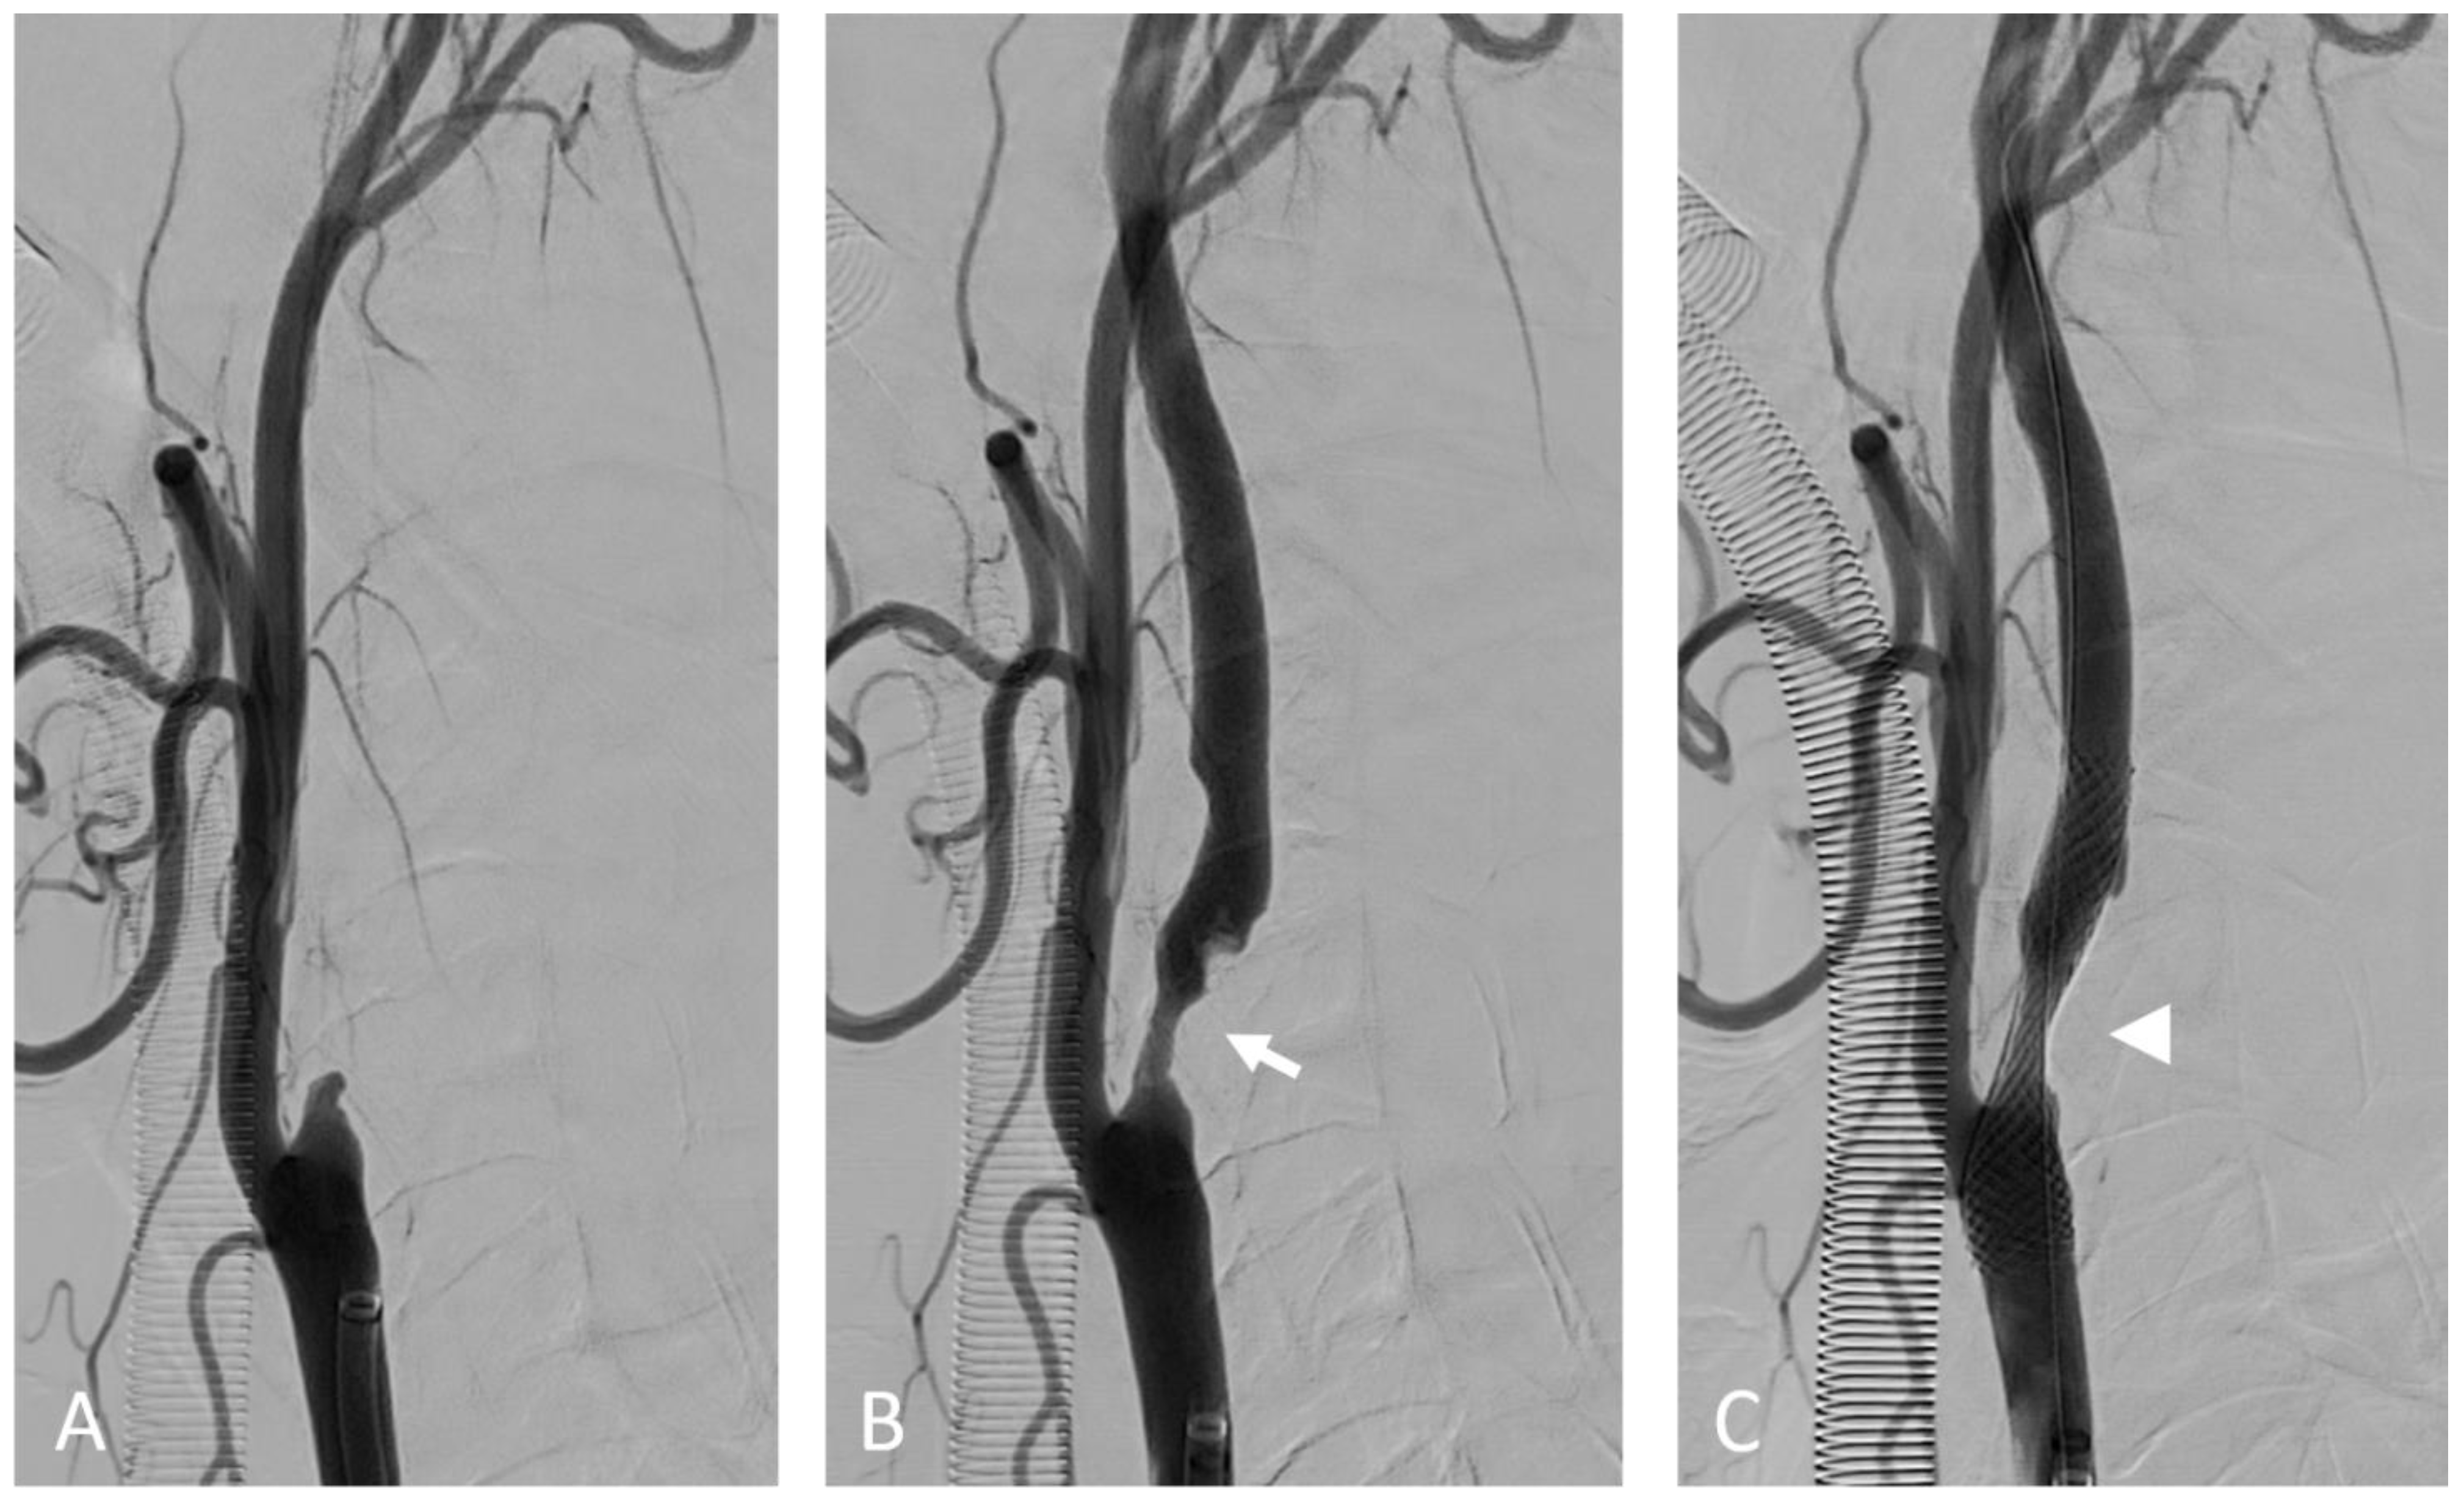

Figure 4.

Internal carotid artery occlusion, digital subtraction angiography: acute thrombotic occlusion of the left internal carotid artery (A) causing sudden neurologic deficit in a 77-year-old patient. The serigraphy performed after mechanical thrombectomy and recanalization of the artery (B) highlights an ulcerated atherosclerotic plaque of the carotid bulb (arrow). After the administration of intravenous boluses of antiplatelet agents and heparin, a self-expanding stent (arrow) was placed in correspondence to the ulcerated plaque (C).